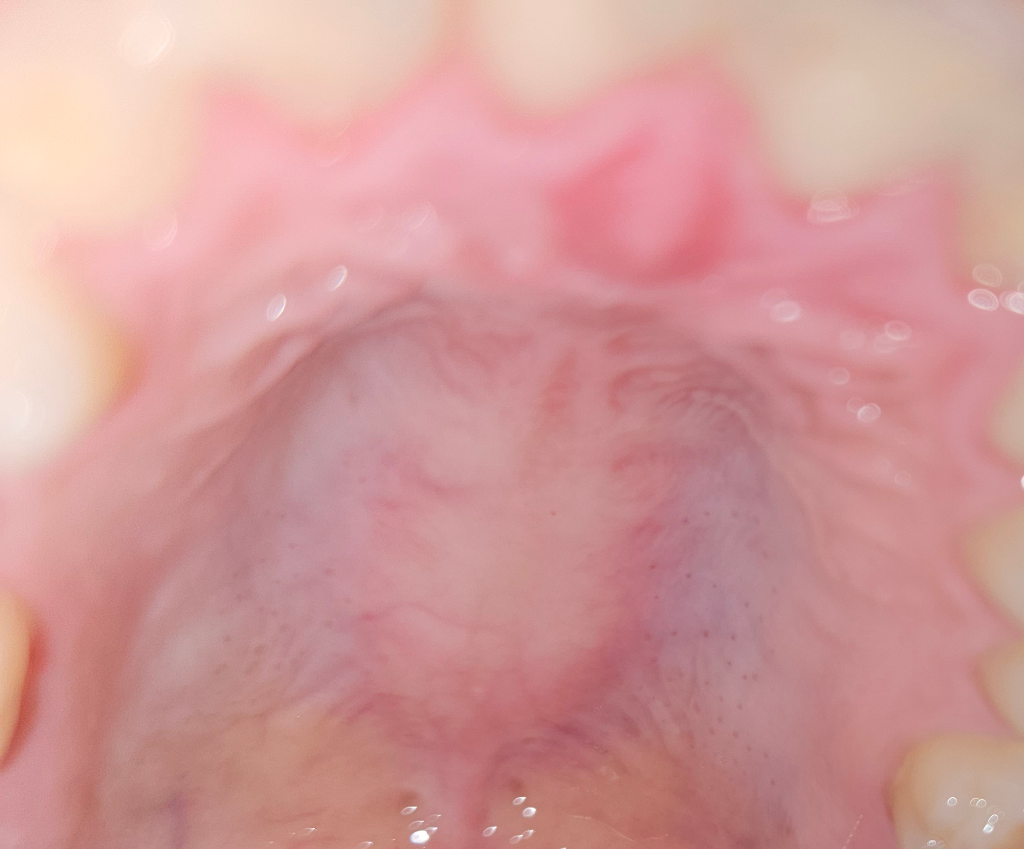

입천장에 작은 혹 1일차 좀 더 기다려 보면 가라앉나요?

일어나 보니 입천장 위에 작은 혹이 났는데 혀로 꾹 누르면 욱신거리는 정도? 단순 피로 때문일까요? 기다려 보면 나을지, 얼마정도 지속되면 내원치료를 해야 할 지 궁금해요.

사진으로 봤을 경우에는 잇몸에 자극이 되었거나 잇몸 안쪽에 염증이 있을 수 있습니다.

저부위는 신경이 지나가는 곳입니다. 아마도 뜨거운거나 자극적인 음식을 드셔서 저부위에 발적이 일어 난거 같으니 시간이 지나면괜찮아 지실꺼에요.